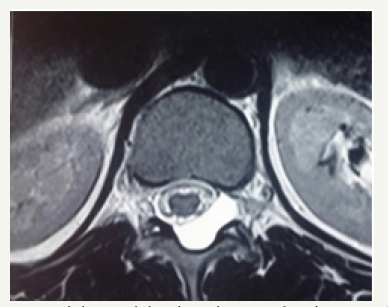

Figure 1c: Axial T2 weighted MR images showing extradural arachnoid cyst.

19 year male presented with a history of lower back pain of 6 months duration. It was insidious in onset, gradually progressive with mild weakness of both lower limbs. He had a past history of fall from a tree with sustained injury to back 10 years ago. On examination, he had paraparesis with power (grade 4/5). There were no bladder and bowel disturbances. Other physical findings were not remarkable. MRI dorsal spine with screening of the entire spine showed a small, elongated, well defined CSF signal intensity extradural cystic lesion at D11-12 level suggesting arachnoid cyst. The lesion was compressing the dorsal spinal cord from behind (Figure 1a-1c).

Magnetic resonance imaging appears to be effective as an initial modality for diagnosing arachnoid cysts and does not require the intrathecal injection of contrast medium. It can define the anatomical relationship to surrounding structures. The imaging characteristics of arachnoid cysts are similar to those of CSF signal intensity. Epidural fat capping of the lesion at its superior and inferior poles can be seen on sagittal T1-weighted MR images, which further suggests its extradural location. The presence of vertebral body scalloping and expansion of the neural foramina bilaterally from osseous remodelling suggests a longstanding mass effect from the lesion.